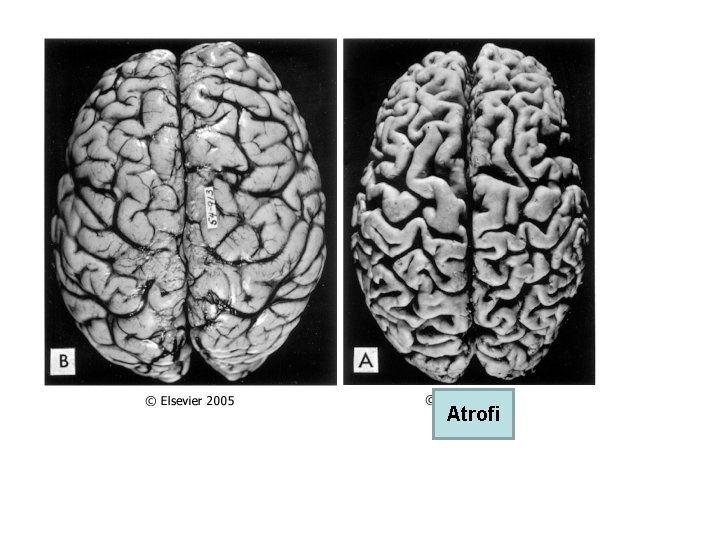

• Kullanılmama atrofisi: Alçıya alınan ekstremitede kas atrofisi ve osteoporoz • Denervasyon atrofisi: Travmatik sinir kesisi • Kan akımı azalmasına bağlı atrofi: İskemi Ateroskleroz ileri yaşta beyin atrofisi • Yetersiz beslenmeye bağlı atrofi • Endokrin stimülasyon kaybına bağlı atrofi: Menopozda endometrium atrofisi, vaginal epitel atrofisi • Senil atrofi: Yaşlanma ile kalp ve beyinde hücre kaybı • Basınç atrofisi: Tümörler çevre dokuya basınç yaparak atrofiye sebep olur.

Atrofi